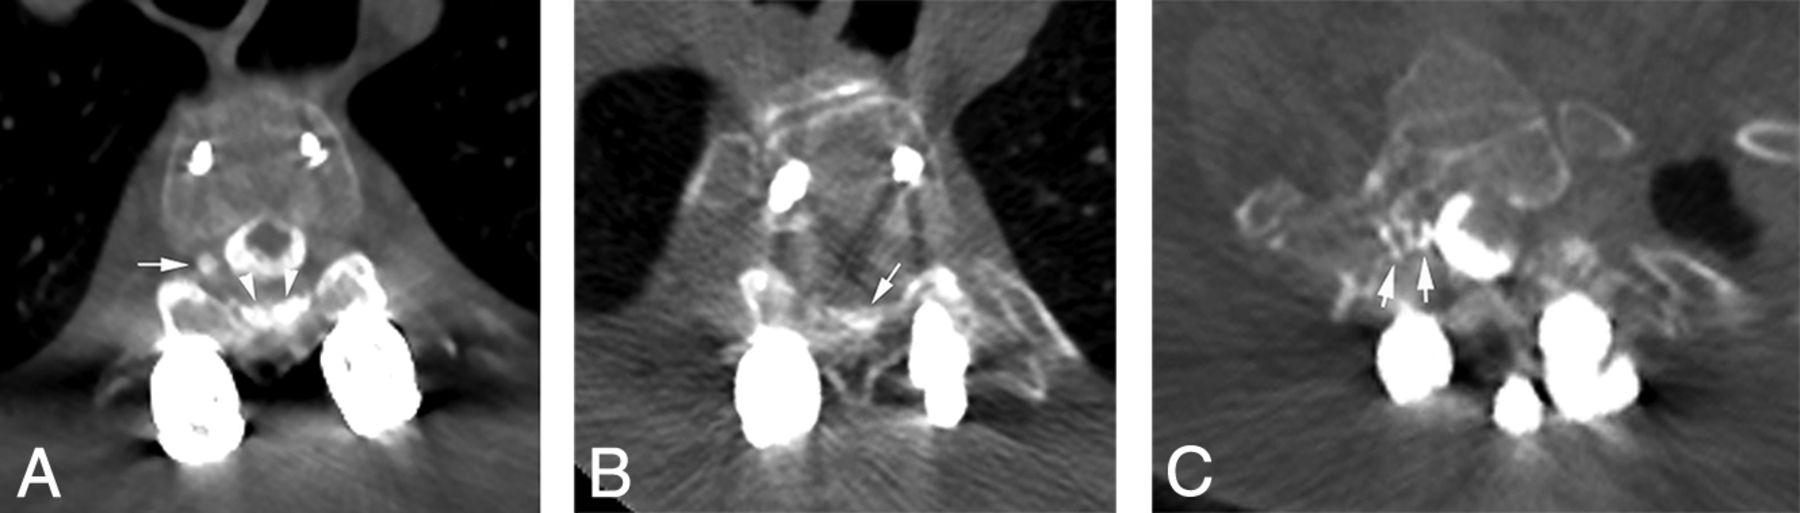

Value of decubitus CTM in diagnosing a CSF-venous fistula. A, An axial conventional CTM at the T10–T11 level shows bilateral meningeal diverticula without evidence of a CSF-venous fistula. B, An axial MR imaging myelogram with intrathecal gadolinium shows similar findings. C, A right-decubitus CTM in the axial oblique plane shows a right-sided CSF-venous fistula with a paravertebral course (arrows).